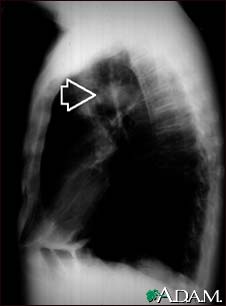

Pulmonary mass - side view chest X-ray

This individual has a mass in the upper part of the lung. Although the cause of the mass can be suspected, based on this person's history, there are many diseases that can produce lung lesions.